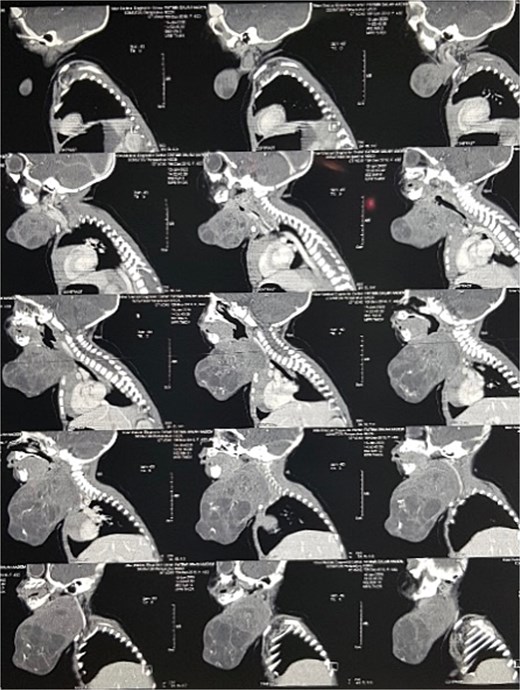

On examination of the neck, the patient has a large anterior neck mass measuring 15 × 20 cm in diameter, with apparent lobulations and a cystic nature. The face appeared edematous, and the trachea was not palpable, with stridor evident on auscultation (Fig. 1). A soft tissue ultrasound revealed a cystic swelling that is not separable from the adjacent thyroid gland. A subsequent CT scan of the neck showed highly lobulated soft tissue that enhances with calcifications (Fig. 2).

Contrast-enhanced sagittal CT scan of the neck showing the cervical teratoma.